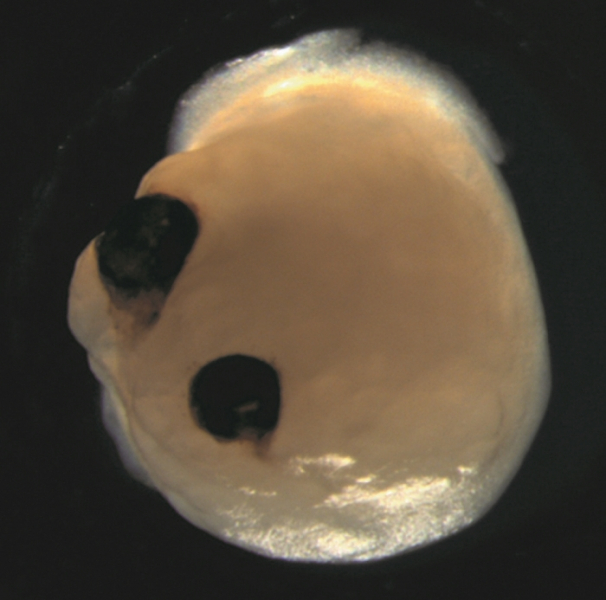

Изменив свои протоколы и добавив ретинола ацетат в культуральную среду, команда успешно наблюдала рост двух двусторонне-симметричных зрительных чашек в органоидах мозга. Эти зрительные чашки напоминали развитие структур глаза у человеческих эмбрионов, проливая свет на сложный процесс формирования глаза.

"Наша работа подчеркивает удивительную способность органоидов мозга создавать примитивные сенсорные структуры, чувствительные к свету и содержащие типы клеток, схожие с теми, что встречаются в организме", — говорит Гопалакришнан. "Эти органоиды могут помочь в изучении взаимодействия мозга и глаза во время эмбрионального развития, моделировании врожденных заболеваний сетчатки и создании специфических для пациента типов клеток сетчатки для персонализированного тестирования лекарств и трансплантационной терапии".